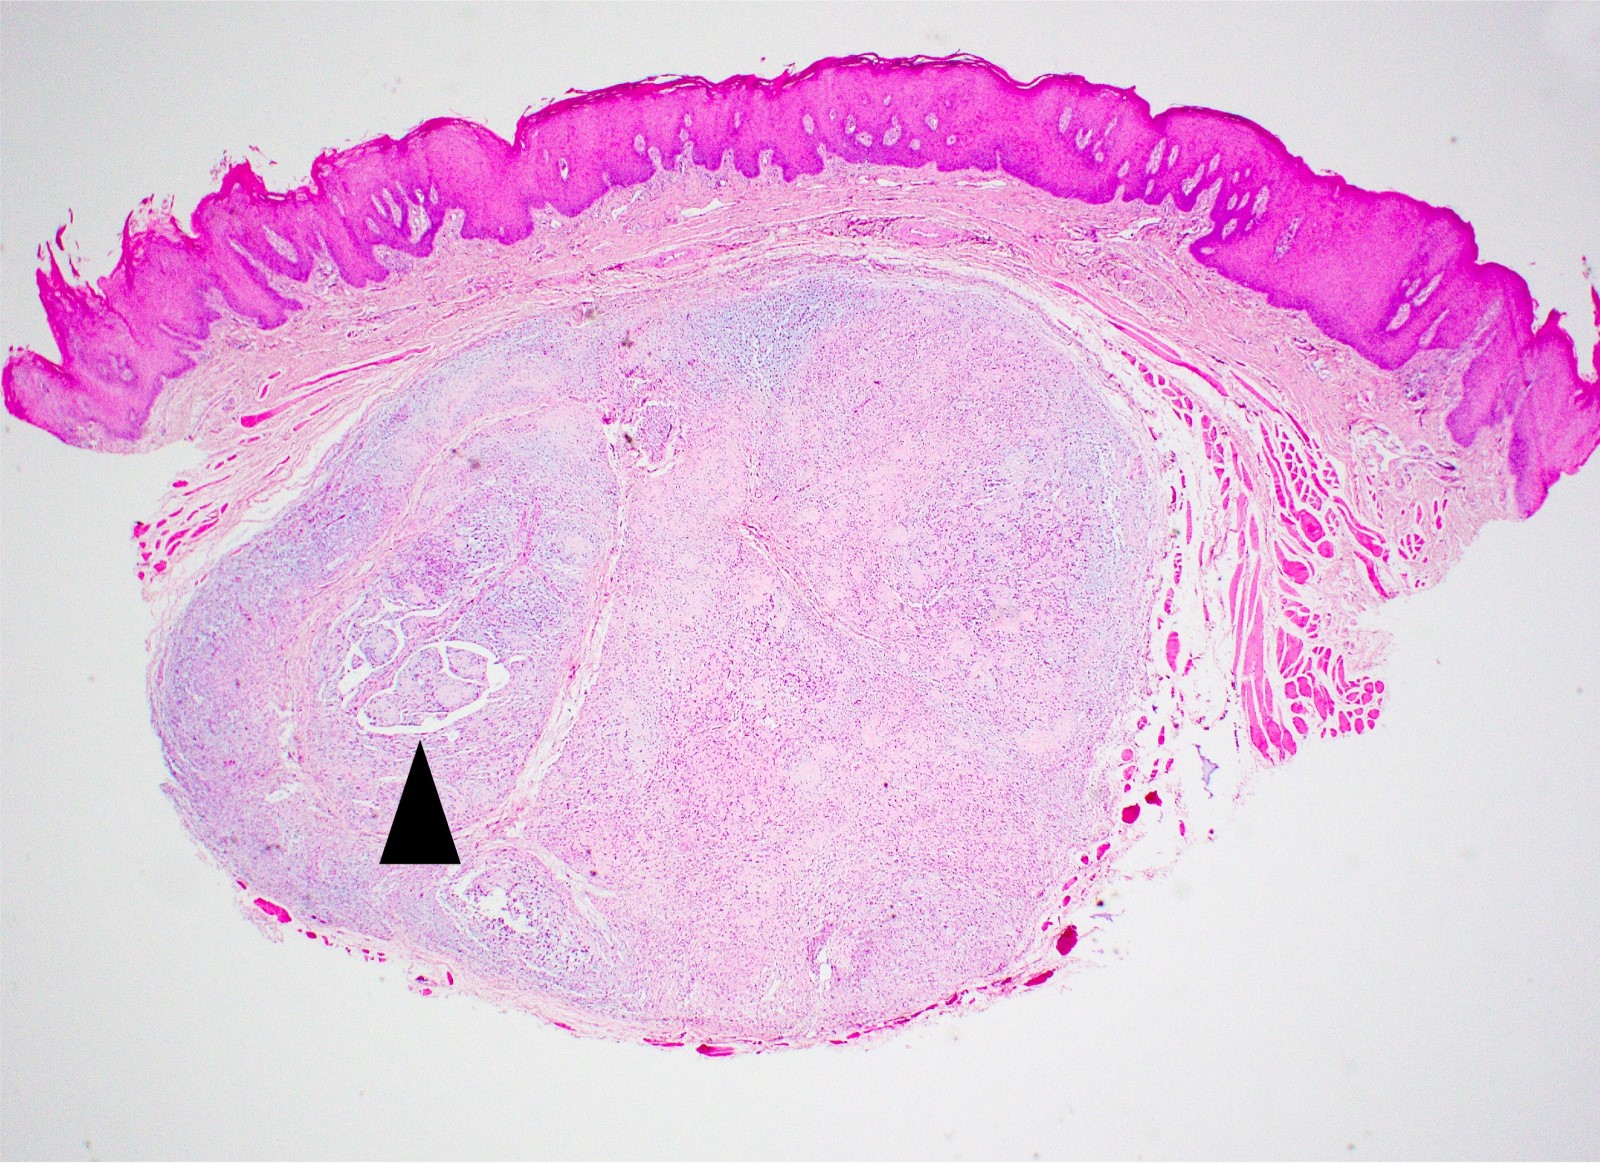

Microscopic (histologic) description

- Well demarcated tumor, often entrapped within skeletal muscle and frequently multilobulated (Am J Surg Pathol 2018;42:1297, Head Neck Pathol 2015;9:315)

- Stromal background may be hyalinized or demonstrate mucoid, myxoid or chondromyxoid areas

- Cords, strands or sheets of oval, round, fusiform or polygonal bland cells, sometimes arranged in a reticular / net-like or globoid pattern (Am J Surg Pathol 2018;42:1297)

- Myxoglobulosis-like changes have been noted (Virchows Arch 2003;442:302)

- May focally demonstrate fine calcifications, cellular atypia, necrosis, multinucleated giant cells (Am J Surg Pathol 2018;42:1297, Head Neck Pathol 2015;9:315, Oral Surg Oral Med Oral Pathol Oral Radiol Endod 1996;82:417)

- Cystic, slit-like spaces or hemorrhagic areas often noted (Head Neck Pathol 2014;8:329)

- Mitotic figures not seen (Head Neck Pathol 2015;9:315)

Microscopic (histologic) images